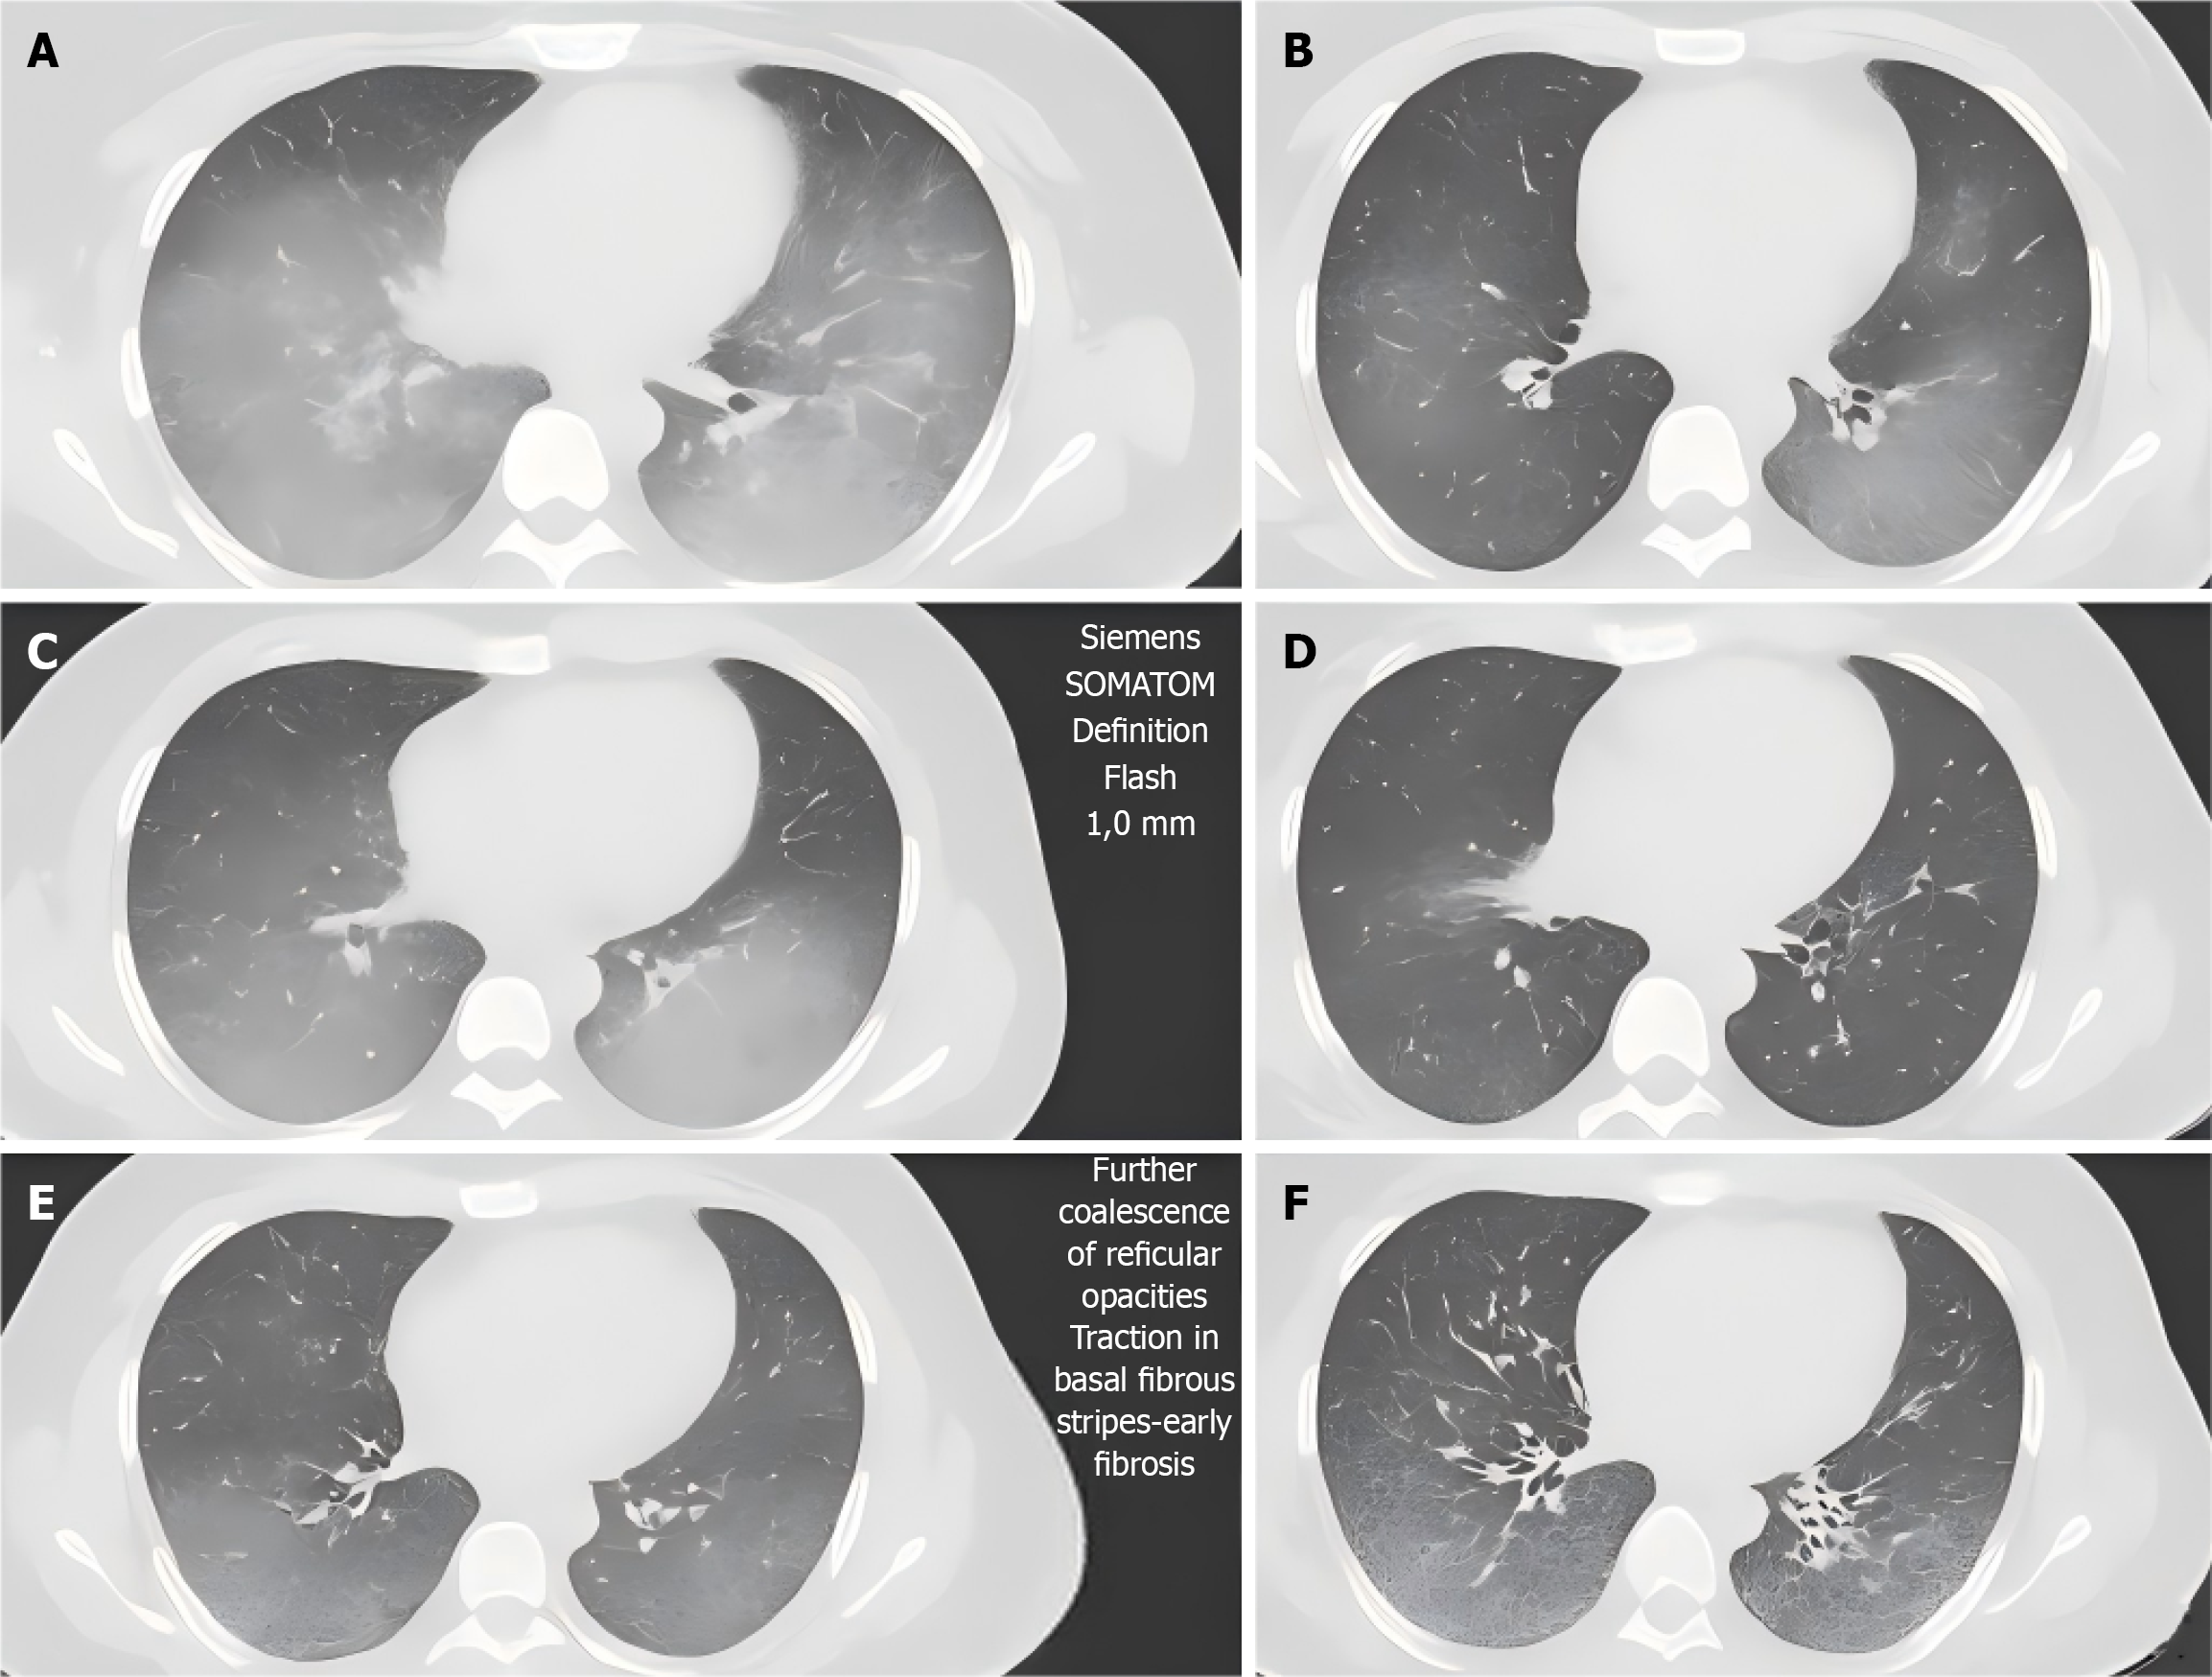

Figure 1 Detection of high-resolution computed tomography imaging indicators in typical cases.

A and B: Diffuse grid shadow with ground-glass shadow in middle and lower fields of both lungs, and subpleural distribution was dominant (at enrollment); C and D: The ground-glass opacity was partially absorbed, but fibrous bands were increased in the basal segment, suggesting early fibrosis (6th month); E and F: Shows further confluency of the grid shadows, with the formation of traction branches and the appearance of honeycomb-like changes with continuous progression of fibrosis (12th month). Scan parameters: Siemens Somatom Definition Flash, 1.0 mm layer thickness, 120 kVp, 200-250 mAs. Double blind evaluation of quantitative lesion extent.